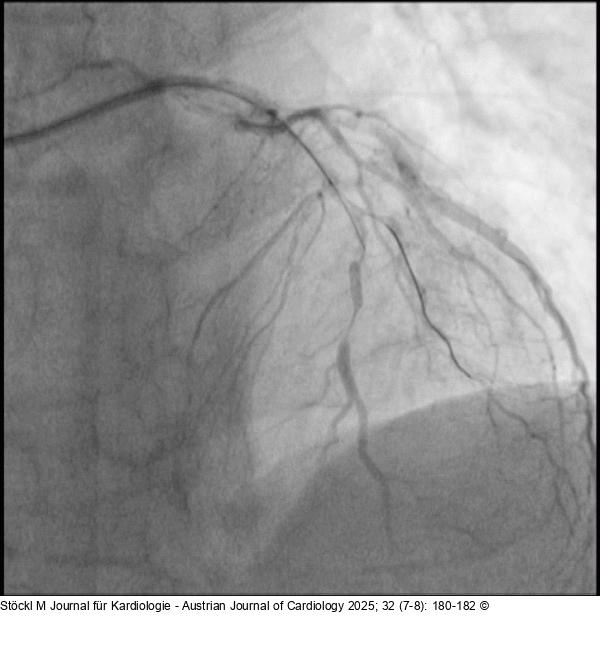

Abbildung 2: LAD LAD: im mittleren Gefäßabschnitt langstreckig verkalkt, wirksam stenosiert |

Abbildung 2: LAD

LAD: im mittleren Gefäßabschnitt langstreckig verkalkt, wirksam stenosiert |